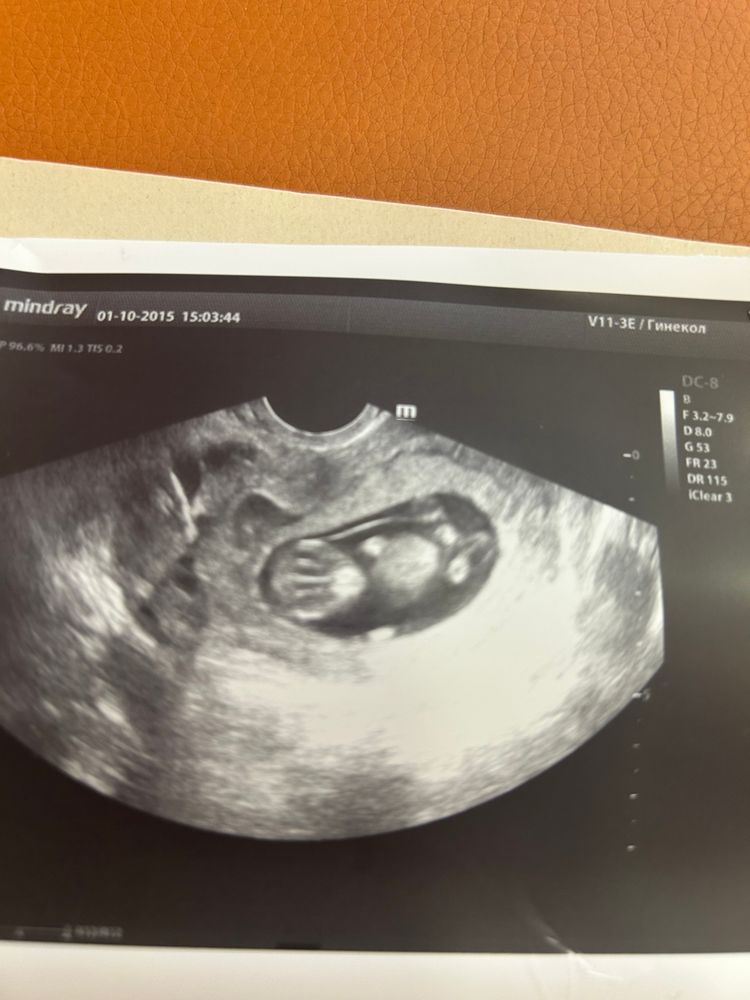

Узи 11 недель

Фото классное, но смотрят сбоку. На этой фотографии это вполне может быть пуповина.

Ну тут не видно бугорка, тут снимок в анфас, а нужен сбоку)

На таком фото не видно, да и рано ещё, на 13 неделе на фото сбоку видно бугорок